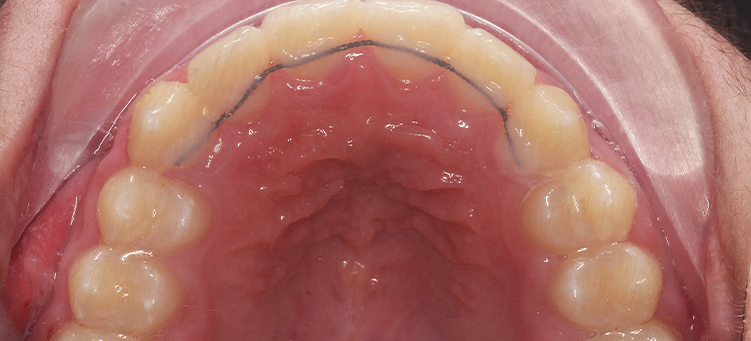

Исправления скученности верхних и нижних резцов